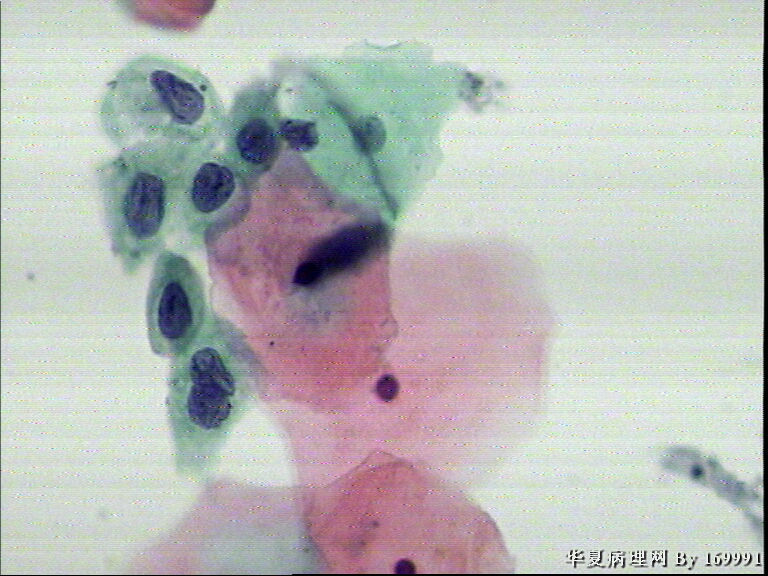

宫颈液基,患者,23岁,宫颈中糜

• 宫颈液基,患者,23岁,宫颈中糜图3

图3

我感觉报HSIL有点高了,就细胞的形态来看,核增大深染的基本上还是中层以及接近表层的细胞,结合患者年龄,我认为报LSIL更好一些。不知道对不对,请各位老师指教啦!

大家都看得不错。最高可能是CINII级,看活检了。

感觉像高级别,但患者年龄太小。ASC-H